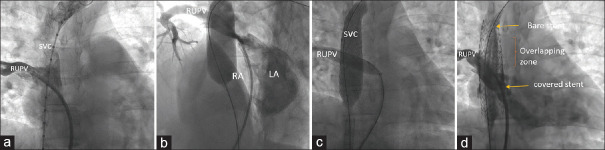

Superior vena cava (SVC) type of sinus venosus defect (SVD) associated with anomalous right upper pulmonary vein (RUPV) drainage is often corrected by open-heart surgery. Transcatheter-covered stent exclusion is an attractive emerging alternative using a covered stent in the lower end of SVC to close the SVD and redirect the RUPV to the left atrium. The location of SVD posterosuperior to oval fossa challenges its transthoracic echocardiographic identification and delays its diagnosis to adult age. Lifestyle adult diseases, including atherosclerosis, elevate the left ventricular end-diastolic pressures and increase the pretricuspid left-to-right shunt. Surgery addresses coronary stenosis and SVD, but lifestyle diseases increase surgical risks. We diagnosed significant coronary stenosis in three patients with SVD. These patients underwent percutaneous management of both lesions. Nonsurgical management of SVD and ischemic heart disease is a more viable alternative than a high-risk surgery in adults with comorbidities.